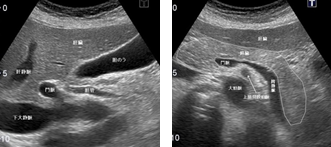

超音波とCTだけでなく、より専門的な超音波内視鏡、ERCP(内視鏡的逆行性胆管膵管造影)、PTC(経皮経肝胆管造影)、血管造影、胆道・膵管内視鏡等を行っています。